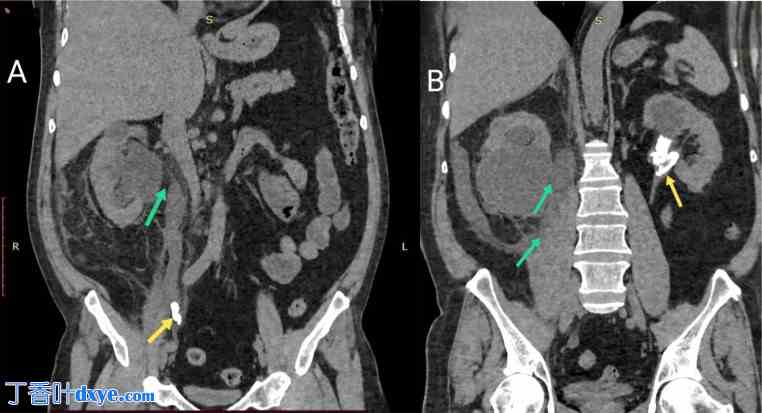

图 2.

(A, B) 普通 CT 腹部平片 (冠状位) 显示右侧髂腰肌附近尿液积聚(绿色箭头)。右侧输尿管远端可见结石(斯坦街状征),左肾可见结石(黄色箭头)。